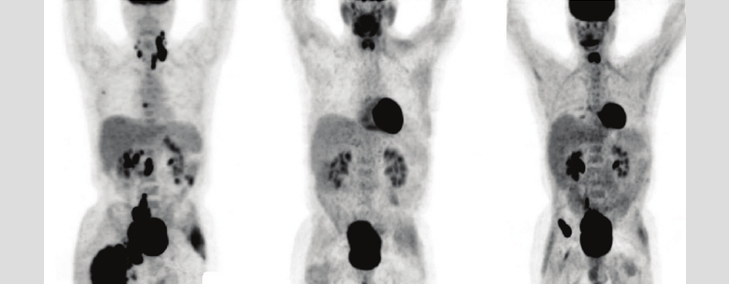

FDG PET

What Is an FDG PET-CT SCAN?

An FDG PET-CT SCAN uses 18F-FDG (18F-Fluorodeoxyglucose), a radiotracer which is an analogue of glucose. In this scan, a small amount of radioactive FDG is injected in the body and its distribution is seen in the body using the PET-CT scanner.